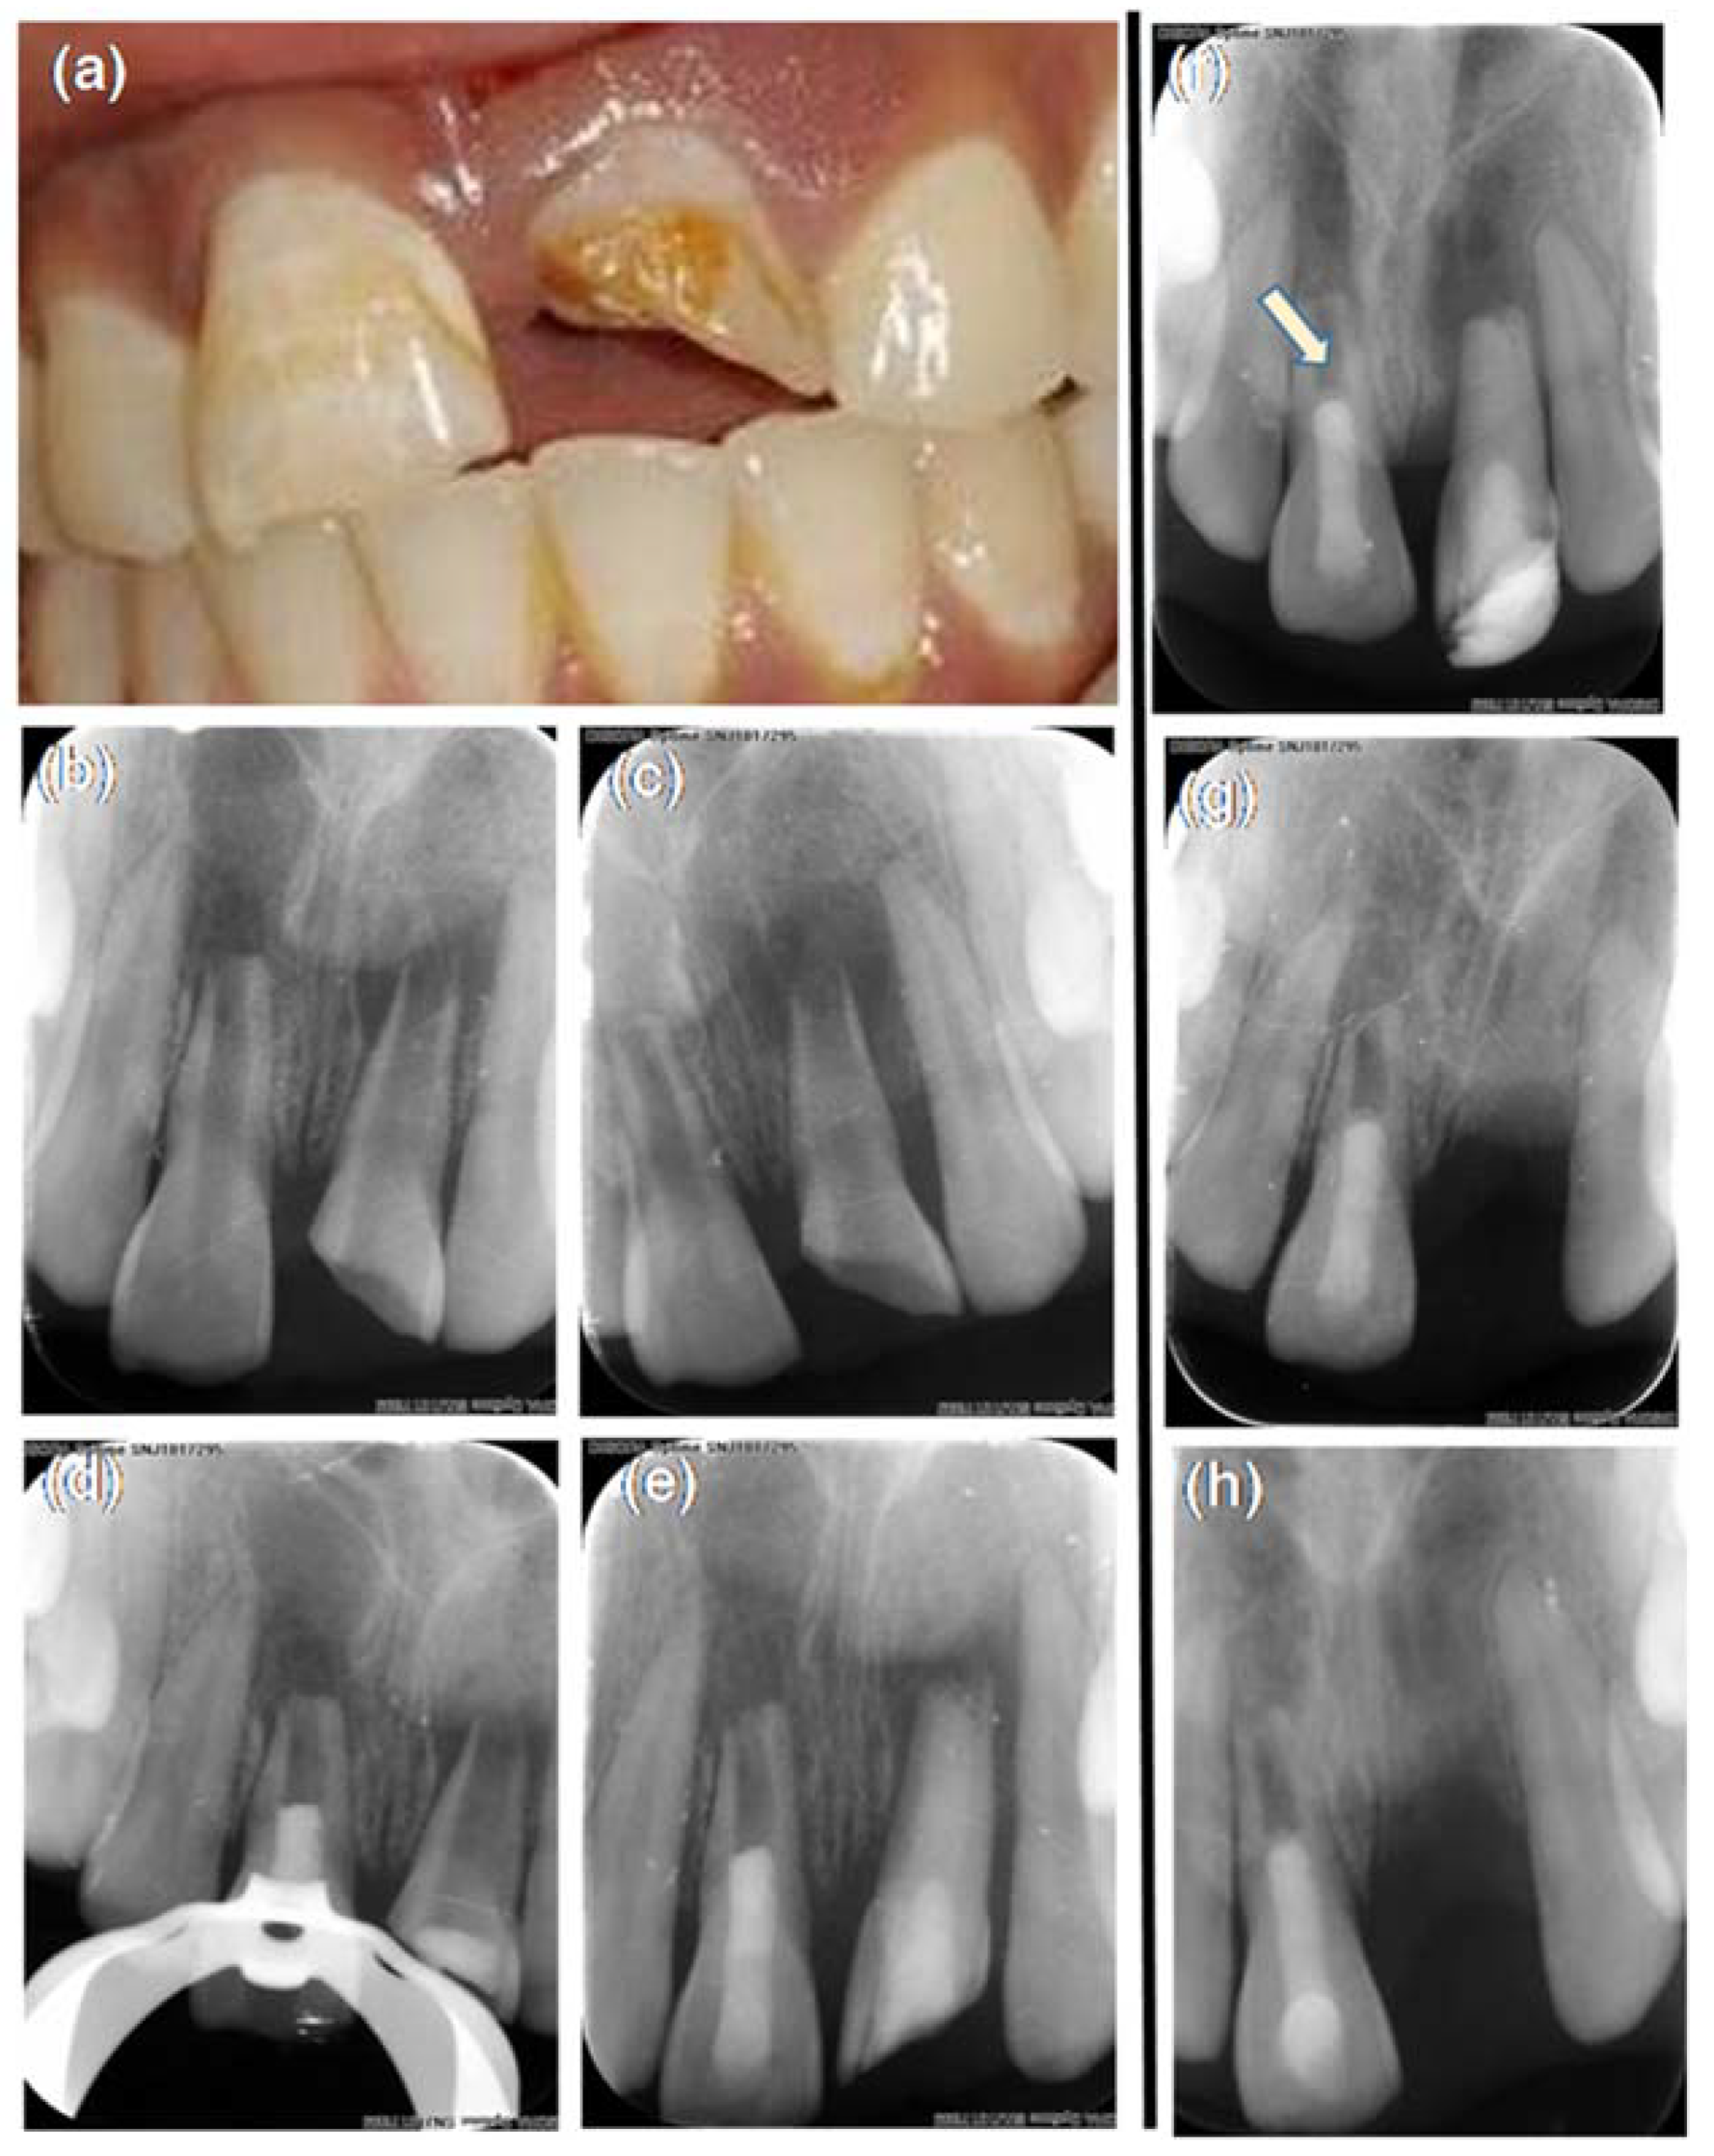

Figure 1.

Intraoral periapical radiograph (IOPA) images of preoperative and a three-year follow up of REP in 11. (a) pre-operative photograph of maxillary central and lateral incisors; (b,c) pre-operative IOPA of teeth 11 and 21; (d) IOPA showing a coronal seal after placement of HAM in 11; (e) immediate postoperative IOPA of 11; (f) IOPA at a three-month follow up. The arrow is pointing to the calcific barrier above the Biodentine; (g) 19 month follow up IOPA; (h) three-year follow up IOPA.

The patient was asymptomatic when reviewed after 15 days in relation to tooth #11. At the three-month follow up, the patient was asymptomatic with no signs of swelling or sinus tracts in relation to #11 (Figure 1f). The patient was lost to follow up and returned to the clinic at 19 months. The patient was assessed at 19 months (Figure 1g) and at 36 months (Figure 1h) wherein the patient continued to be asymptomatic in relation to tooth #11. The patient responded to electric pulp vitality and cold testing methods, which was reproducible multiple times. The intra oral radiographic examination revealed healing of periapical lesion, thickening of dentinal walls as well as a mineralized dentin bridge formation over Biodentine™ (Figure 1f).